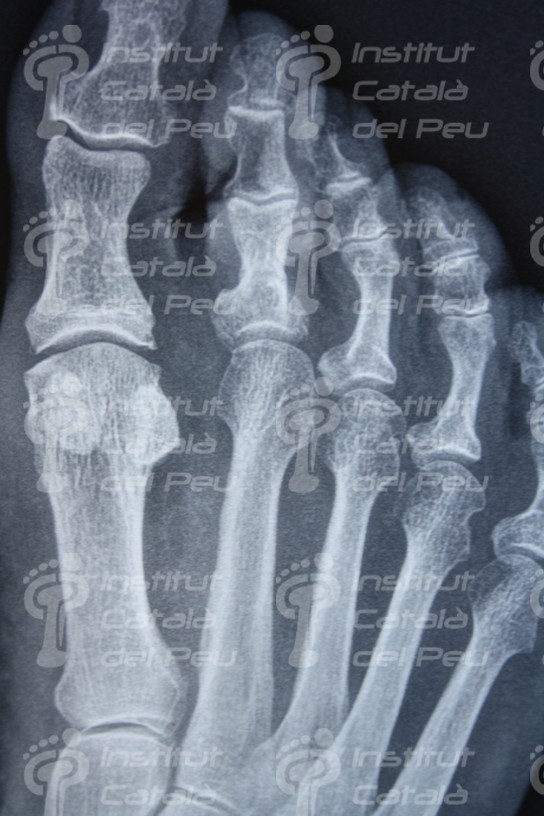

En el examen radiológico, se le realizó una proyección dorso-plantar en carga y una lateral, donde se podía apreciar la luxación de la articulación interfalángica proximal y una formula metatarsal de índex minus. A la paciente se le diagnóstico dedo en martillo irreductible y se le expuso la opción de operar. La técnica de intervención fue una artroplastia con fijación mediante aguja de Kirschner conjuntamente con una tenotomía del Extensor largo de los dedos por técnica MIS (mínima incisión). Se realizó la documentación necesaria (derecho de imagen, consentimiento informado, analítica y radiografías) y se le explicaron las pautas a seguir antes y después de la intervención.

Proyección dorso-plantar en carga. Observe la luxación de la articulación interfalángica proximal del segundo dedo.